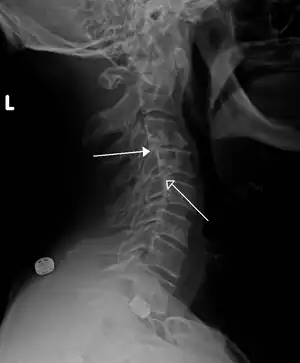

| Grade 1 retrolistheses of C3 on C4 and C4 on C5 | |

A retrolisthesis is a posterior displacement of one vertebral body with respect to the subjacent vertebra to a degree less than a luxation (dislocation). Retrolistheses are most easily diagnosed on lateral x-ray views of the spine. Views where care has been taken to expose for a true lateral view without any rotation offer the best diagnostic quality.

Grading

Since the vertebral body in a retrolisthesis moves in a posterior direction, the grading used for spondylolistheses is of little use. It is however useful to divide the anterior to posterior dimension of the intervertebral foramina (IVF) (4) into four equal units. A posterior displacement of up to ¼ of the IVF is graded as Grade 1, ¼ to ½ as Grade 2, ½ to ¾ as Grade 3, ¾ to total occlusion of the IVF as Grade 4. Alternatively, a measurement of the amount of displacement can also made by measuring the bone displacement in millimetres.